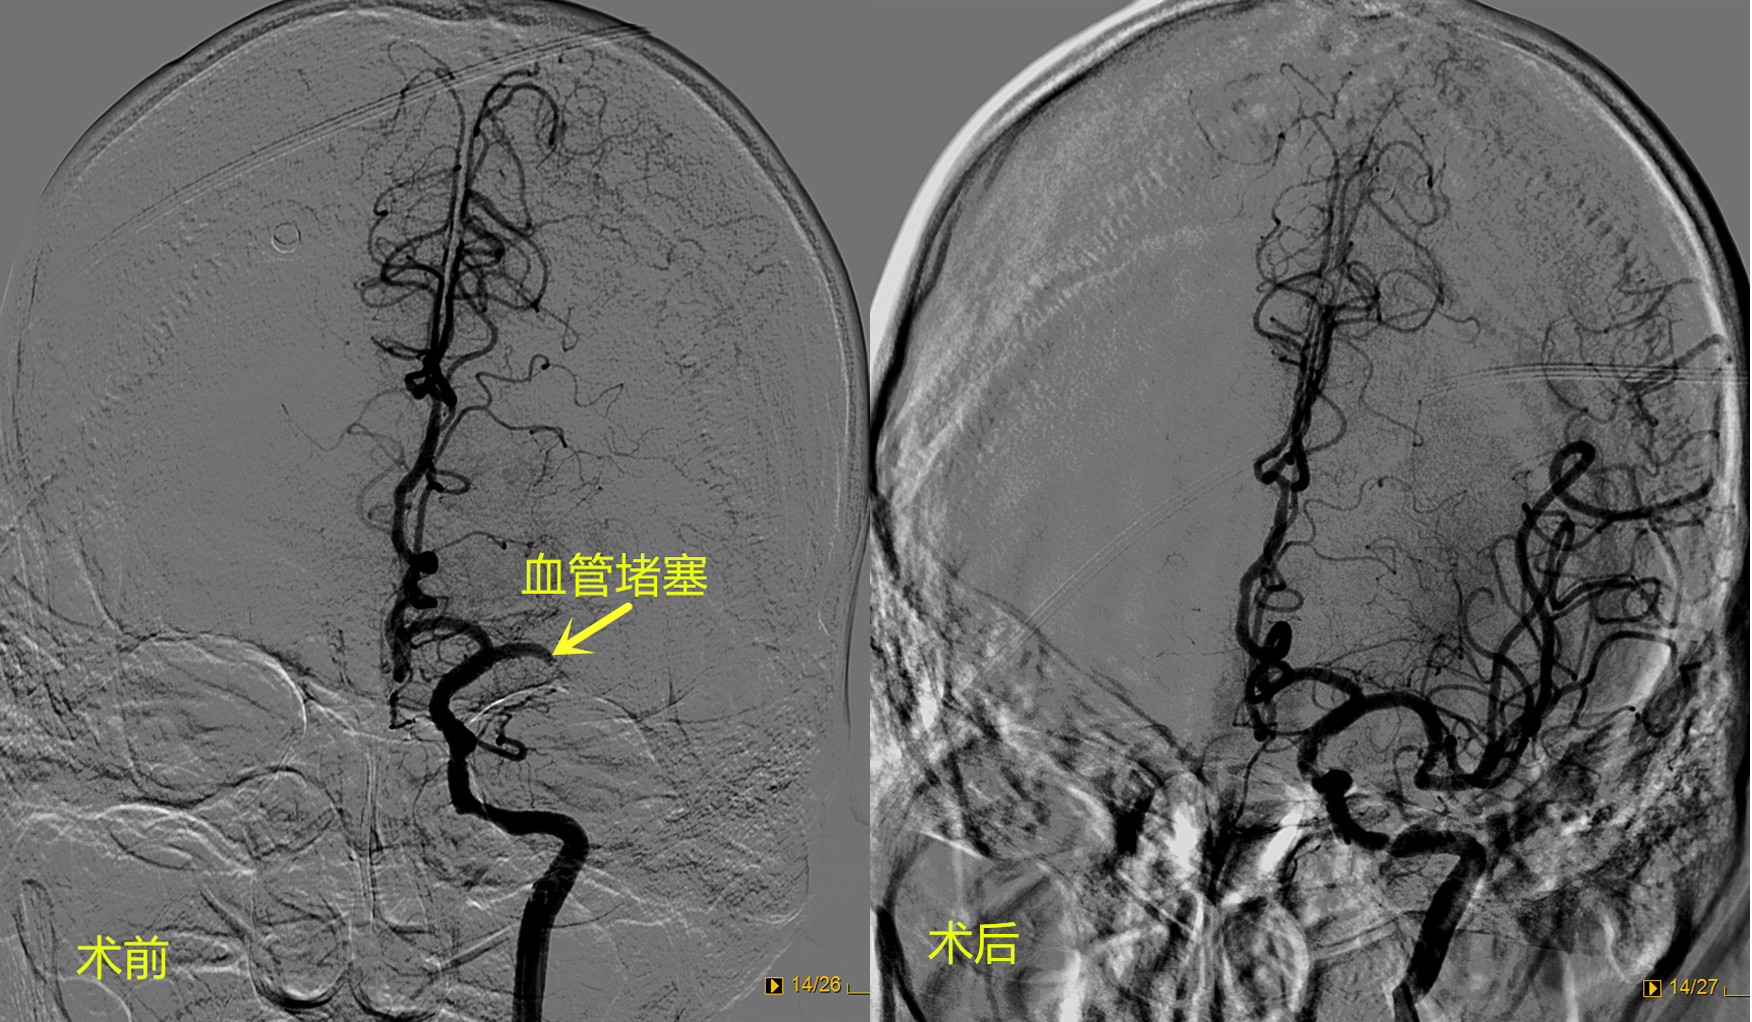

81岁的巩大爷突然出现言语不清、右侧肢体完全瘫痪,家人紧急送至我院急诊科。立即启动卒中绿色通道,紧急进行了颅脑CT检查,考虑为心脏栓子脱落导致脑梗死,卒中小组立即为巩大爷进行了静脉溶栓。考虑到栓子比较大,单纯静脉溶栓无法将栓子溶解,医生认为可以进一步采取介入取栓治疗。但巩大爷年龄大,合并多年的心脏病,手术的难度和风险较高,与家属沟通后,先进行脑血管造影,术中发现患者左侧大脑主干血管堵塞,静脉溶栓药物没能把栓子溶开,介入团队医生立即为巩大爷进行了介入取栓手术,取出2块栓子后再次造影显示左侧大脑血管完全开通,血流恢复正常。